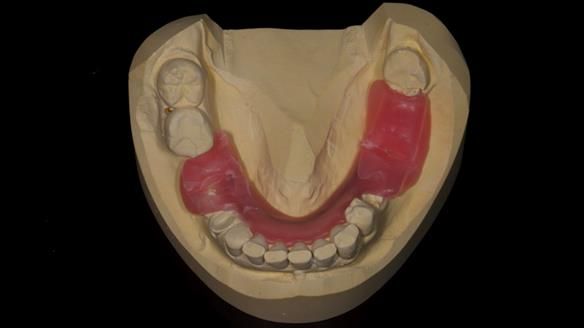

1. Denture design: A custom cobalt-chromium framework was Scandinavian-designed to maximise stability, protect the remaining teeth, and allow for future additions if needed.

3. Definitive alginate impression in custom tray: Used to ensure a well-fitting RPD.

4. Keith’s outcome: The final denture not only improved Keith’s bite, chewing function, and facial aesthetics but also protected his remaining teeth from further damage.